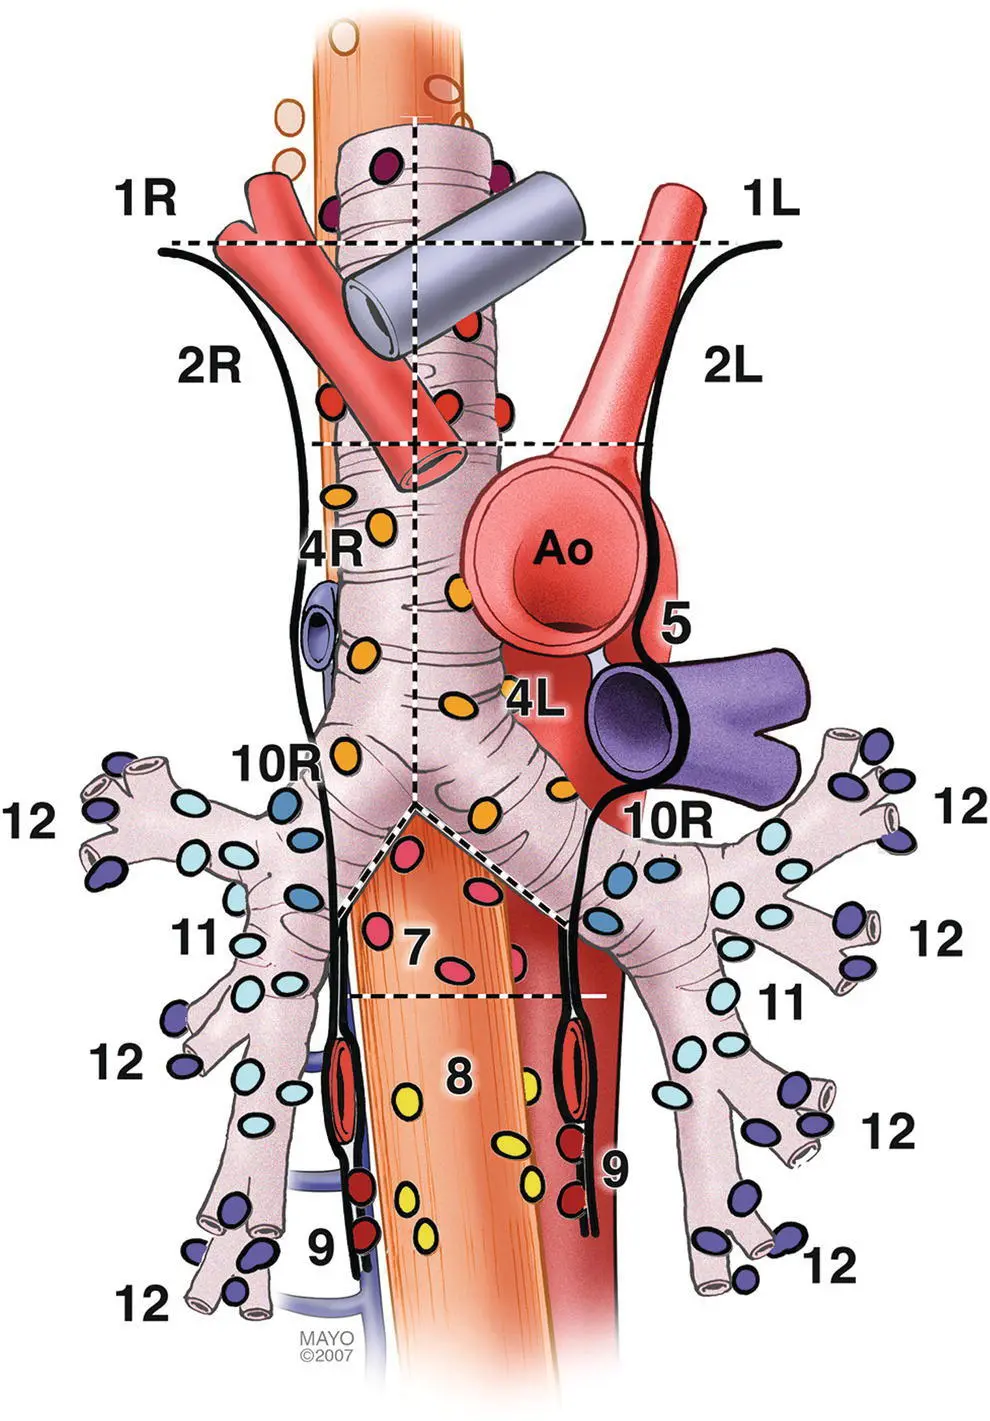

The LNs in the mediastinum were classified in different stations based on surgical and anatomical landmarks for the purpose of staging lung cancer but this schema is now widely used in other chest diseases ( Figure 3.1). The LNs with their respective stations and corresponding anatomical locations are described in Table 3.1.

EUS‐FNA is usually best suited to sample LNs adjacent to the esophagus which runs posterior to the trachea. Because of ultrasound artifacts created by the air‐filled trachea, lesions immediately anterior to the trachea are not well seen. EUS‐accessible stations include 2L, 2R, 4L, 4R, 5, 7, 8, 9, and, sometimes depending on the size, station 6. On the other hand, EBUS‐TBNA can target LNs either anterior or lateral to the trachea to the level of the carina, and alongside the left and right bronchial tree including stations 2L, 2R, 4L, 4R, 7, 10, and 11. Although both procedures overlap in stations 2 L/R, 4 L/R, and 7, in other stations they are complementary, and in combination allow nearly complete mediastinal access.

Figure 3.1 Mediastinal lymph node stations.